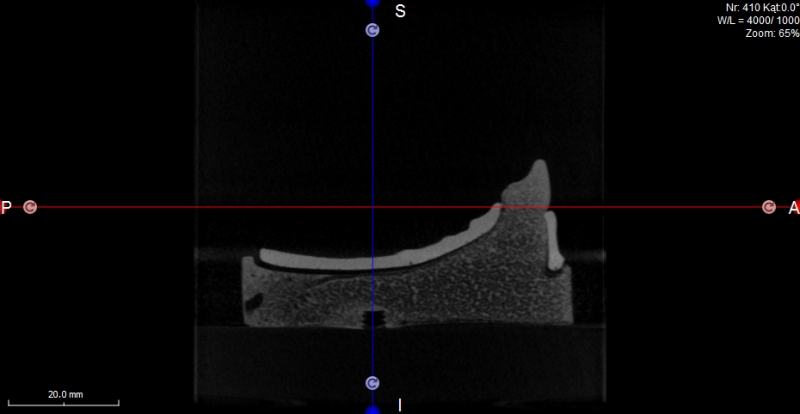

Oferujemy również szablony chirurgiczne przeznaczone do szkoleń z implantacji. Umożliwiają planowanie leczenia implantologicznego i przeprowadzenie szkoleń z wykorzystaniem plików CT, STL oraz druku 3D. Oferujemy nasze modele do szkoleń implantologicznych wraz z plikami DICOM i STL.

Pliki do wykonania szablonów można pobrać z naszej strony internetowej. Możemy je również dostarczyć wraz z modelami. Pliki te dostępne są dla modeli 10-1030, 10-3040, 10-3050, 10-5070,

Istnieje również możliwość dostarczenia szablomów w oparciu o pliki i informację o planowanej procedurze implantologicznej.

Model szczęki z zębami w pozycjach 11, 13, 14, 23, 24, 25 i 27, brakiem zębów w wygojonych pozycjach 21, 22, 26, 15, 16. Umieszczenie dwóch zagłębień imitujących niezagojone zębodoły w pozycjach 17 i 12 umożliwia ćwiczenie implantacji wczesnej i natychmiastowej. Wykonany jest z jednorodnego materiału o właściwościach zbliżonych do kości ludzkiej.  Model pokryty jest śluzówką, którą można nacinać i zszywać. Znakomicie nadający się także do  nauki implantacji odroczonej i planowania leczenia poekstrakcyjnego. Umożliwia również przedstawienie problemów związanych z prawidłowym umieszczeniem implantów pomiędzy koronami sąsiadujących zębów. Model można stosować w najbardziej popularnych na rynku fantomach jak i głowie fantomowej PROMEDICU 11-1000 jak również samodzielnie bez niego.

Poniżej znajduje się przycisk umożliwiający ściągnięcie pliku STL przeznaczonego do wykonanie szablonu do szkoleń implantacyjnych z użyciem modelu.

Numer katalogowy 10-5070